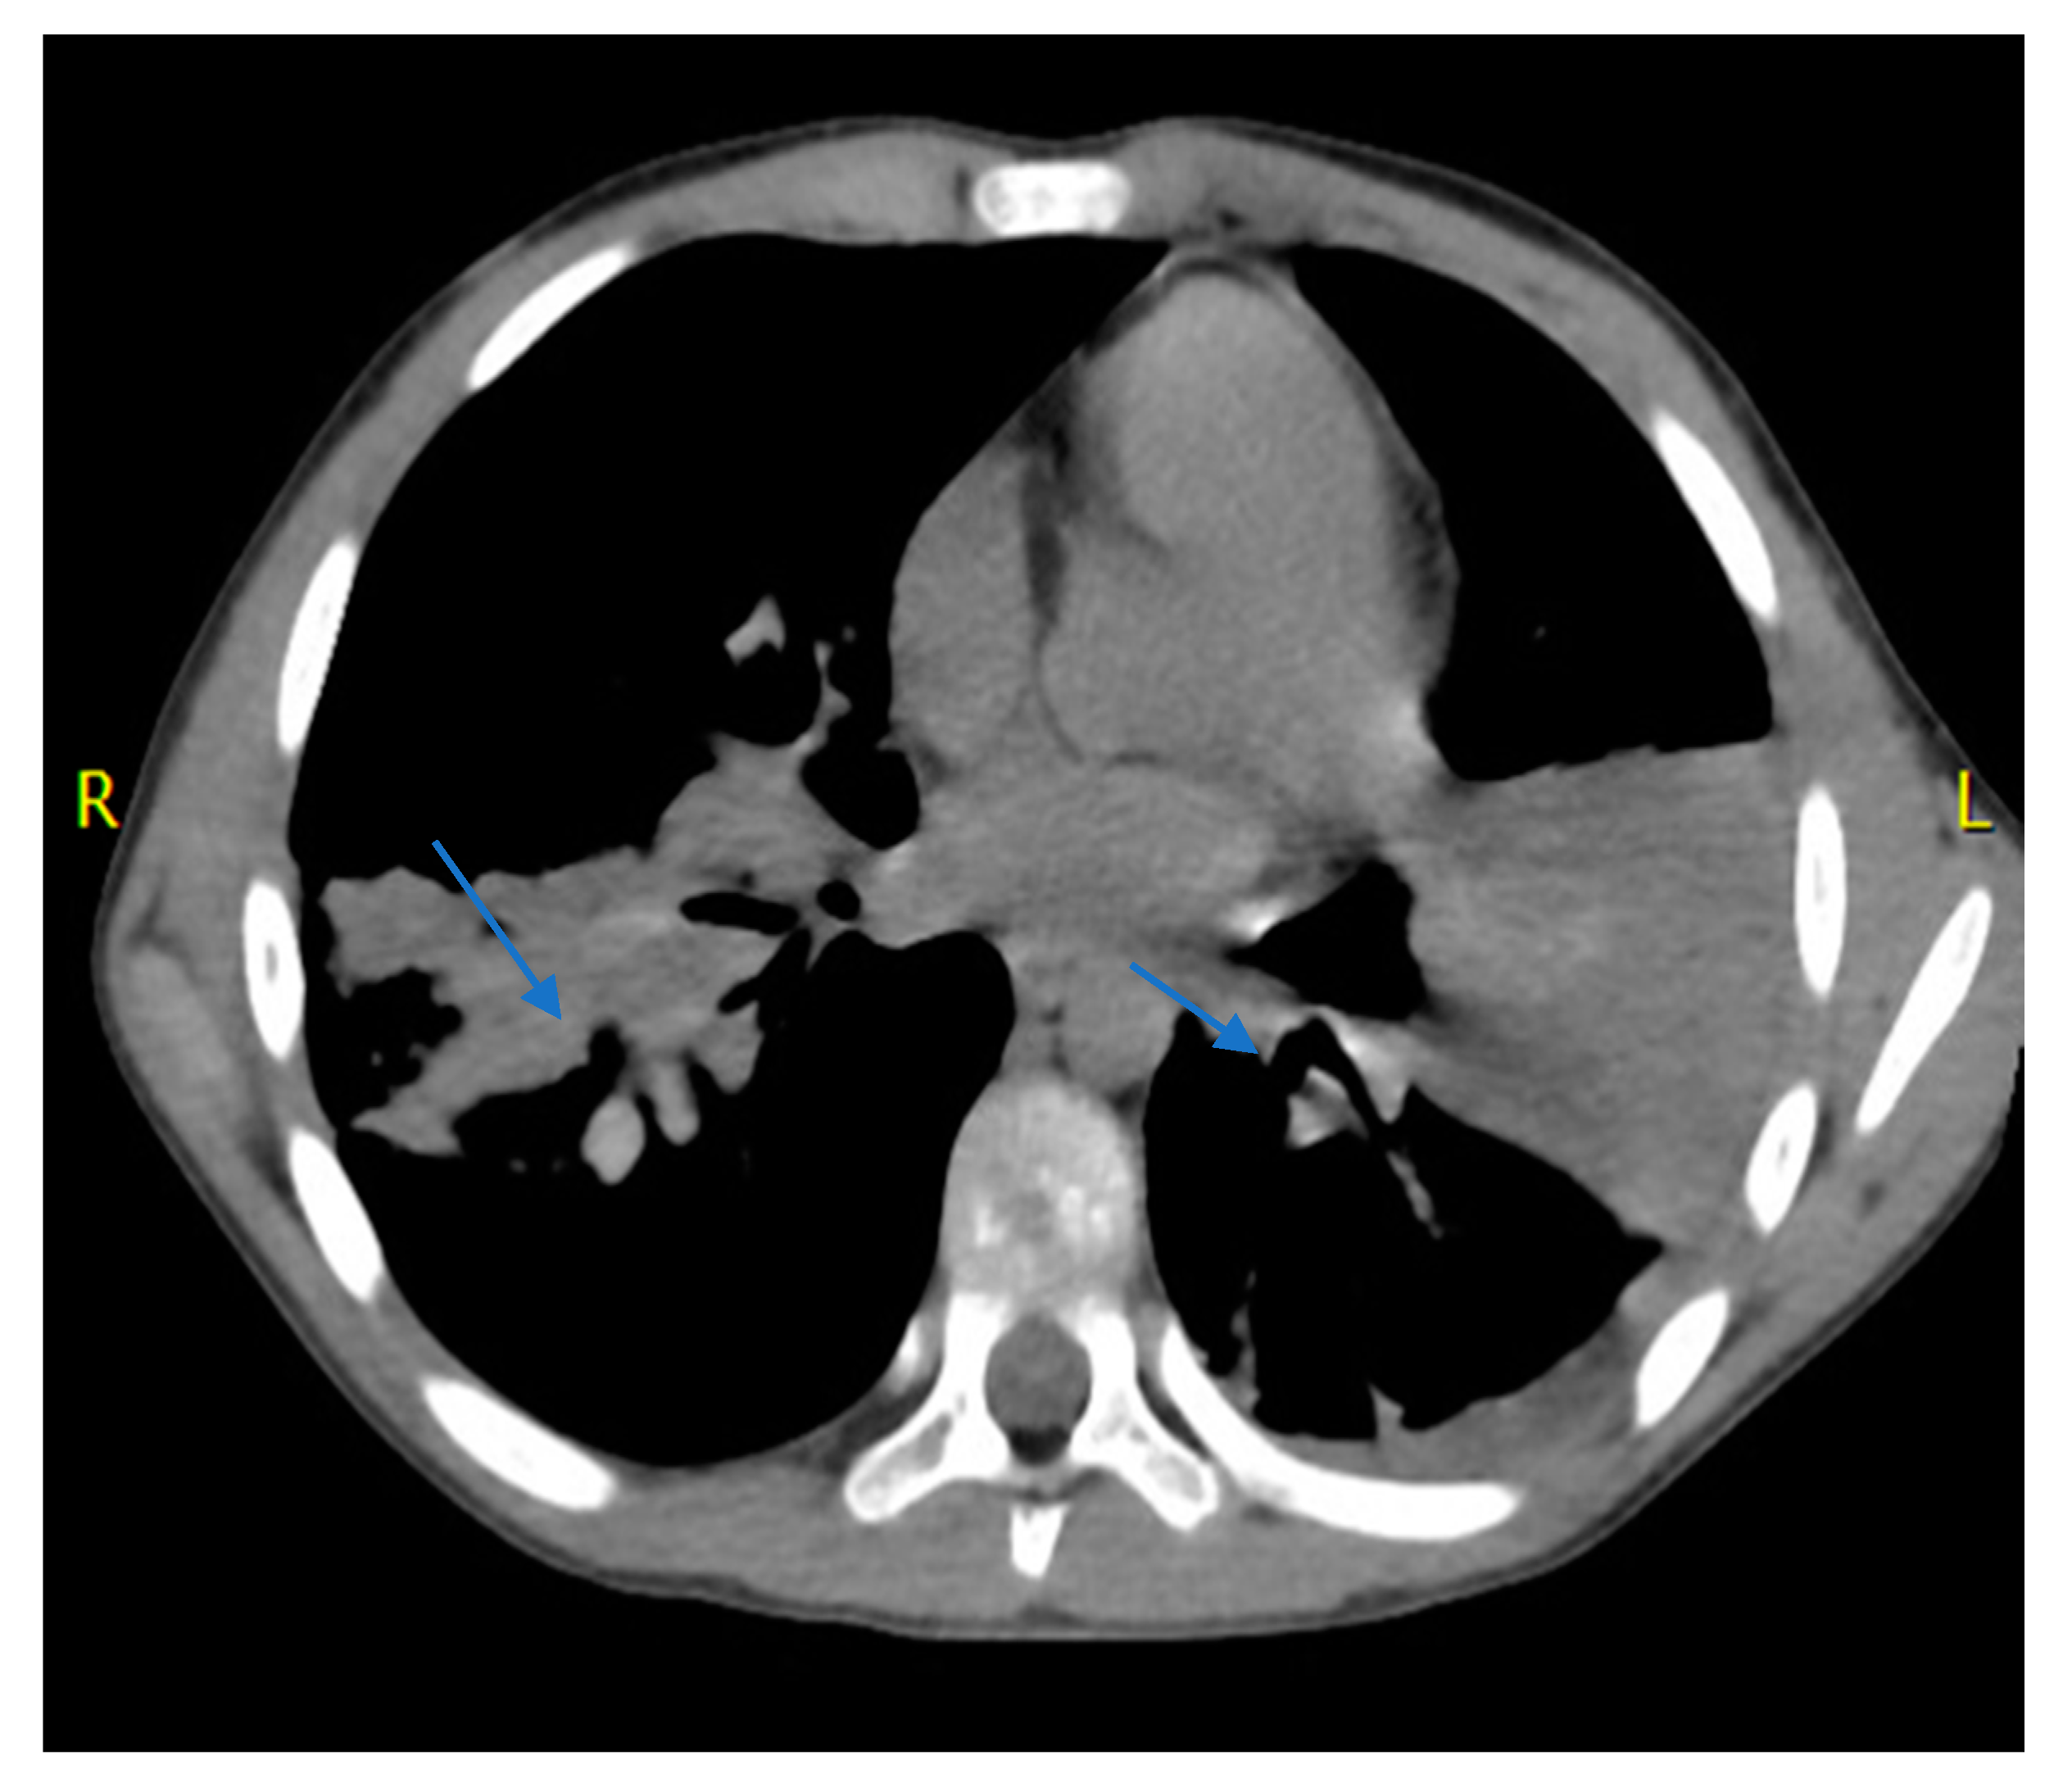

2. Case Report